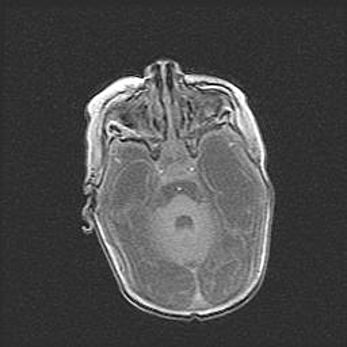

Неполная лизэнцефалия (пахигирия). Открытая гидроцефалия.

Возраст: 17 дней

Вес: 3110 г

Пол: мужской

Окружность головы: 33,5 см

Срок гестации: 35-36 недель

Лизэнцефалия—недоразвитие корковой пластинки и мозговых извилин в результате нарушения миграции нейронов коры. Поверхность мозговых полушарий гладкая. Микроскопически выявляется отсутствие нормальных слоев коры и скопление групп нейронов в подкорковом белом веществе.

Пахигирия—уменьшение числа вторичных извилин. В пораженном полушарии нервные клетки образуют толстый недифференцированный слой с неправильно расположенными нервными волокнами и группами гетеротопных клеток. Нервные клетки незрелые. Белое вещество истончено. При этом нередко аномально развит корково-спинномозговой путь.